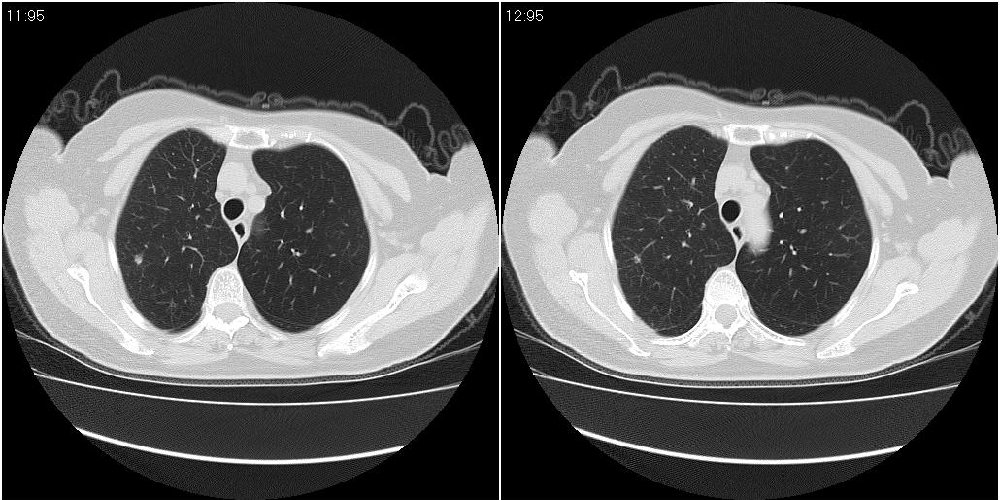

女性,72岁。去年9月份发现肺部病变,诊为肺结核并进行正规治疗至今,但复查后发现ct表现几乎没有变化。

右侧中叶支气管明显狭窄,建议行纤支镜检查!

右中间段支气管局限性狭窄,右中叶支气管亦稍显狭窄,但并未见明显占位表现,半年多了,无变化也许是好事,可能为炎性狭窄,建议继续随访。

双肺继发型tb并右中叶内膜tb,轻度支扩,左下胸膜肥厚粘连。

右中叶炎性改变,支气管狭窄但较光滑,占位可能性不大。

右中间段支气管局限性狭窄,右中叶支气管亦稍显狭窄.

双肺继发性肺结核并右肺中叶节段性肺不张,左下胸膜肥厚粘连。

右肺中叶节段性肺不张,考虑结核或慢性炎症,建议做纤支镜检查。

双肺继发性肺结核并右肺中叶节段性肺不张